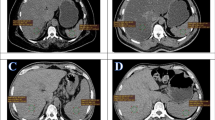

PET uptake values from liver, spleen as well as blood pool of thoracic aorta and CT HU of the liver were measured by drawing three region of interest with a diameter of at least 3 cm in the center of the organ for liver and 1.5 cm for the blood pool in the thoracic aorta. Continuous data (such as BMI, SUVmax, HU) are reported with medians, range and standard deviations while categorical ones are mentioned with counts and percentage. As defined in previous studies fatty liver has been defined as mean liver attenuation measured in HU less than 40 [28,29,30]. Therefore, the steatosis group was defined as study subjects with HU < 40 and the rest have been considered as control group. The maximum standard uptake value (SUVmax) of the thoracic aorta has been considered as reference value for calculation of liver/background SUV ratio (SUVl/b). It has been measured by adding 3 manually drawn ROI to a VOI (Fig. 1).

Fatty liver has been defined as mean liver attenuation measured in Hounsfield Units (HU) < 40. [11C]acetate uptake (A) and CT HU (B) values of the liver were measured by drawing three region of interest (ROI) with a diameter of at least 3 cm within the liver. Three ROIs into the blood pool within the thoracic aorta (C) to measure the SUVmean as background activity for standardization of liver uptake (calculation of liver/background SUV ratio)